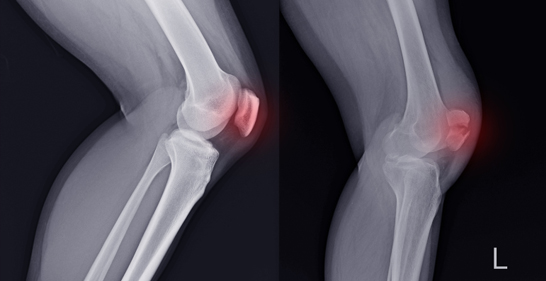

9. Knee Fracture

A break in the patella (kneecap) or other bones around the knee.

Icon Cause: Falls, direct trauma, or sports injuries.

Icon Symptoms: Knee pain, swelling, difficulty extending the leg.

Icon Treatment: Bracing or surgery for displaced fractures.